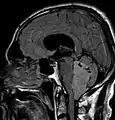

Épendymomes de la fosse postérieure

Les épendymomes localisés dans la fosse postérieure (PF) sont des tumeurs radiologiquement homogènes et bien délimitées, avec des remaniements hémorragiques et d'éventuelles taches de calcification montrant une prise de contraste variable due à la nécrose et à la formation de kystes. Ces tumeurs peuvent être localisées à l'intérieur du quatrième ventricule avec une expansion latérale possible à travers les foramens de Luschka ou le foramen de Magendie. Les épendymomes PF peuvent être divisés en deux sous-groupes en fonction de leur profil épigénétique : les PF de groupe A (PFA) et les PF de groupe B (PFB) [11].